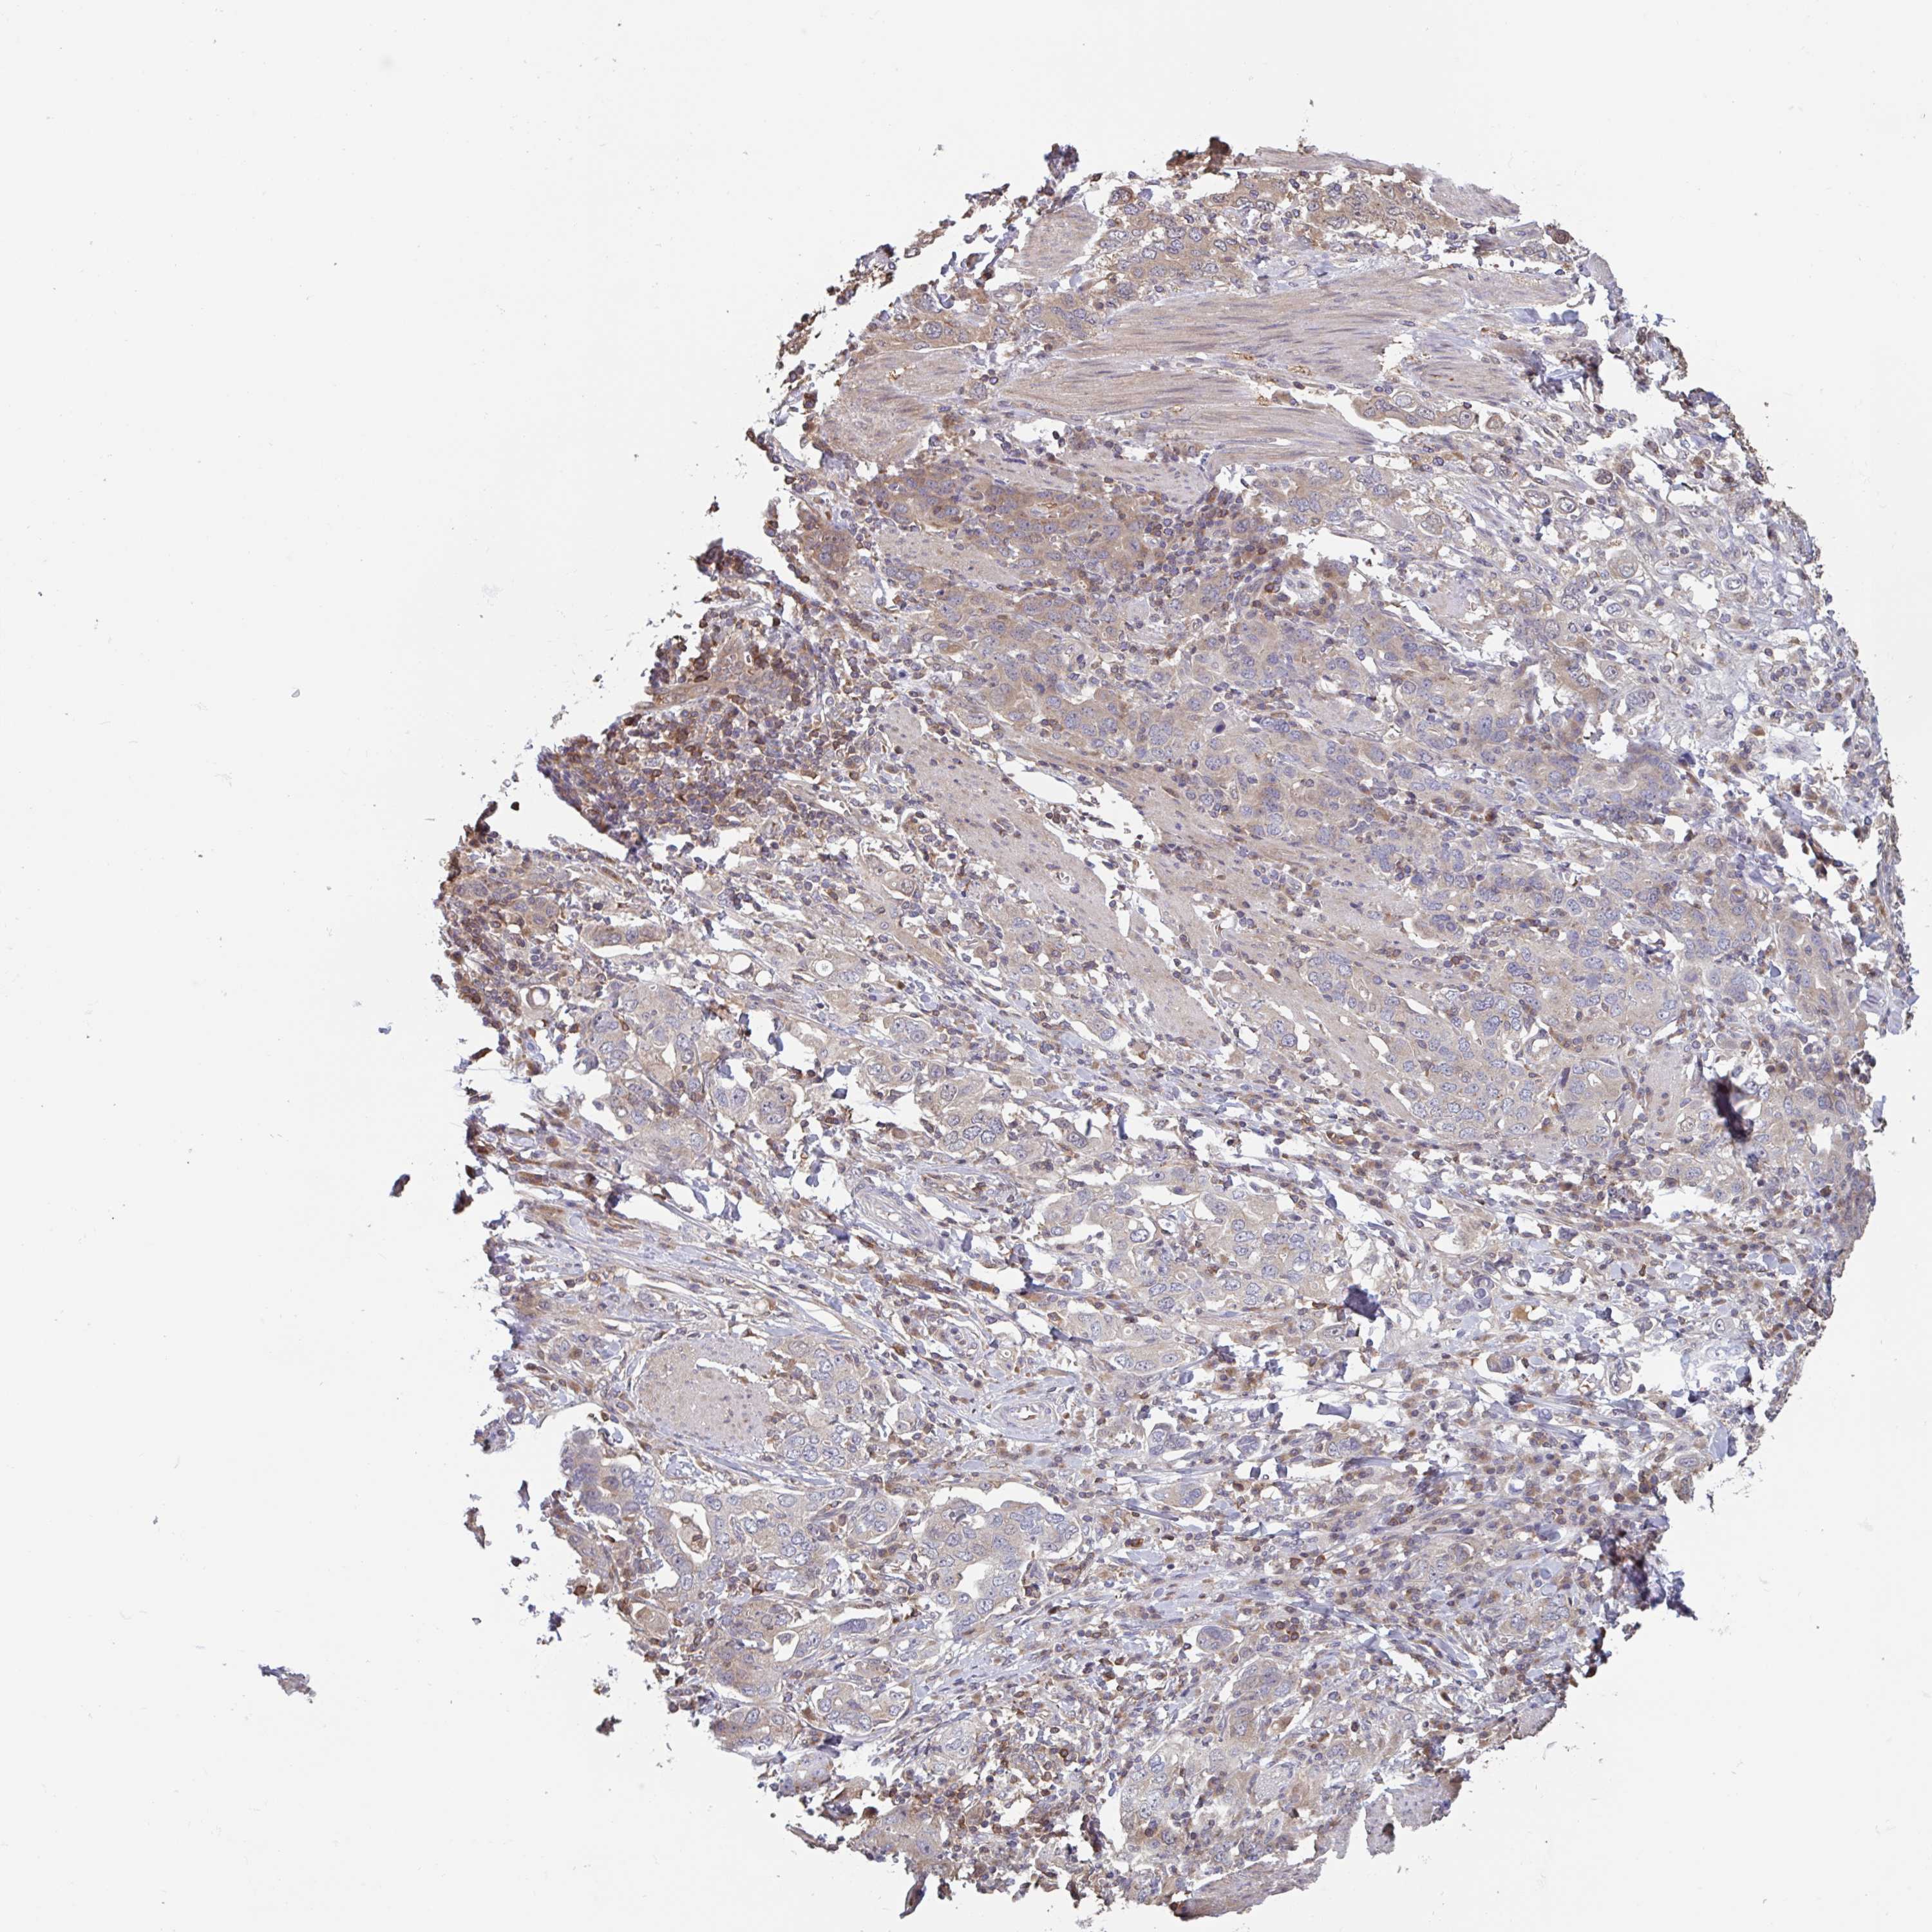

STOMACH CANCER - Protein expressioni

A mouse-over function shows sample information and annotation data. Click on an image to view it in a full screen mode. Samples can be filtered based on level of antibody staining by selecting one or several of the following categories: high, medium, low and not detected. The assay and annotation is described here.

Note that samples used for immunohistochemistry by the Human Protein Atlas do not correspond to samples in the TCGA dataset.

Antibody stainingi

Antibody staining in the annotated cell types in the current human tissue is reported as not detected, low, medium, or high, based on conventional immunohistochemistry profiling in selected tissues. This score is based on the combination of the staining intensity and fraction of stained cells.

Each image is clickable and will lead to virtual microscopy that enables deeper exploration of all samples and also displays staining intensity scores, fraction scores and subcellular localization as well as patient and tissue information for each sample.

Antibody HPA024524

Antibody HPA053090

Staining

High

Medium

Low

Not detected

Intensity

Strong

Moderate

Weak

Negative

Quantity

>75%

75%-25%

<25%

None

Location

Nuclear

Cytoplasmic/membranous

Cytoplasmic/membranous,nuclear

Adenocarcinoma, NOS